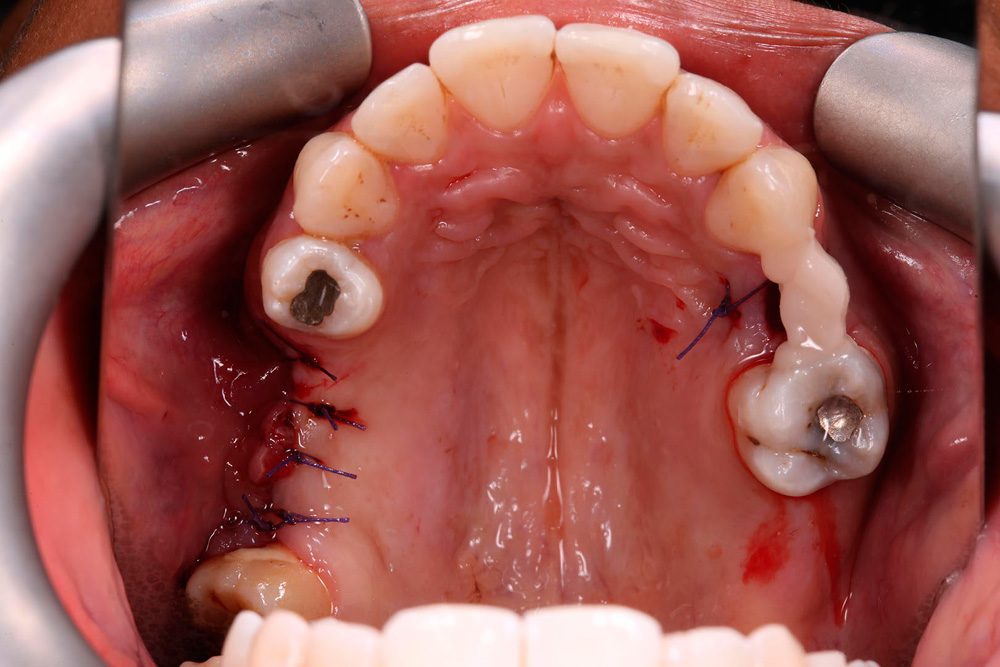

Removing Dental Membrane . Attachment to a periodontally diseased tooth, using barrier devices or membranes to provide space maintenance, epithelial exclusion, and wound stabilization. A dental bone graft is a surgical procedure that involves transplanting bone tissue into the jaw or oral cavity to promote bone growth and regeneration. The membrane will act as a shield to cover the area and hold the graft into the socket. Many stitches will then hold the membrane and graft into place. This depends entirely on the graft material , it is critical on most graft materials but there a newer materials where the graft is both. Read our bone grafting & membrane placement instructions following your procedure. The bone grafting material consists of granules of bone that will fill the entire tooth socket. 4/5 (16) We offer family dental care to protect your oral health.

Attachment to a periodontally diseased tooth, using barrier devices or membranes to provide space maintenance, epithelial exclusion, and wound stabilization. We offer family dental care to protect your oral health. Read our bone grafting & membrane placement instructions following your procedure. The membrane will act as a shield to cover the area and hold the graft into the socket. The bone grafting material consists of granules of bone that will fill the entire tooth socket. A dental bone graft is a surgical procedure that involves transplanting bone tissue into the jaw or oral cavity to promote bone growth and regeneration. This depends entirely on the graft material , it is critical on most graft materials but there a newer materials where the graft is both. Many stitches will then hold the membrane and graft into place. 4/5 (16)

Removing Dental Membrane The membrane will act as a shield to cover the area and hold the graft into the socket. Attachment to a periodontally diseased tooth, using barrier devices or membranes to provide space maintenance, epithelial exclusion, and wound stabilization. A dental bone graft is a surgical procedure that involves transplanting bone tissue into the jaw or oral cavity to promote bone growth and regeneration. We offer family dental care to protect your oral health. The membrane will act as a shield to cover the area and hold the graft into the socket. Many stitches will then hold the membrane and graft into place. 4/5 (16) The bone grafting material consists of granules of bone that will fill the entire tooth socket. This depends entirely on the graft material , it is critical on most graft materials but there a newer materials where the graft is both. Read our bone grafting & membrane placement instructions following your procedure.